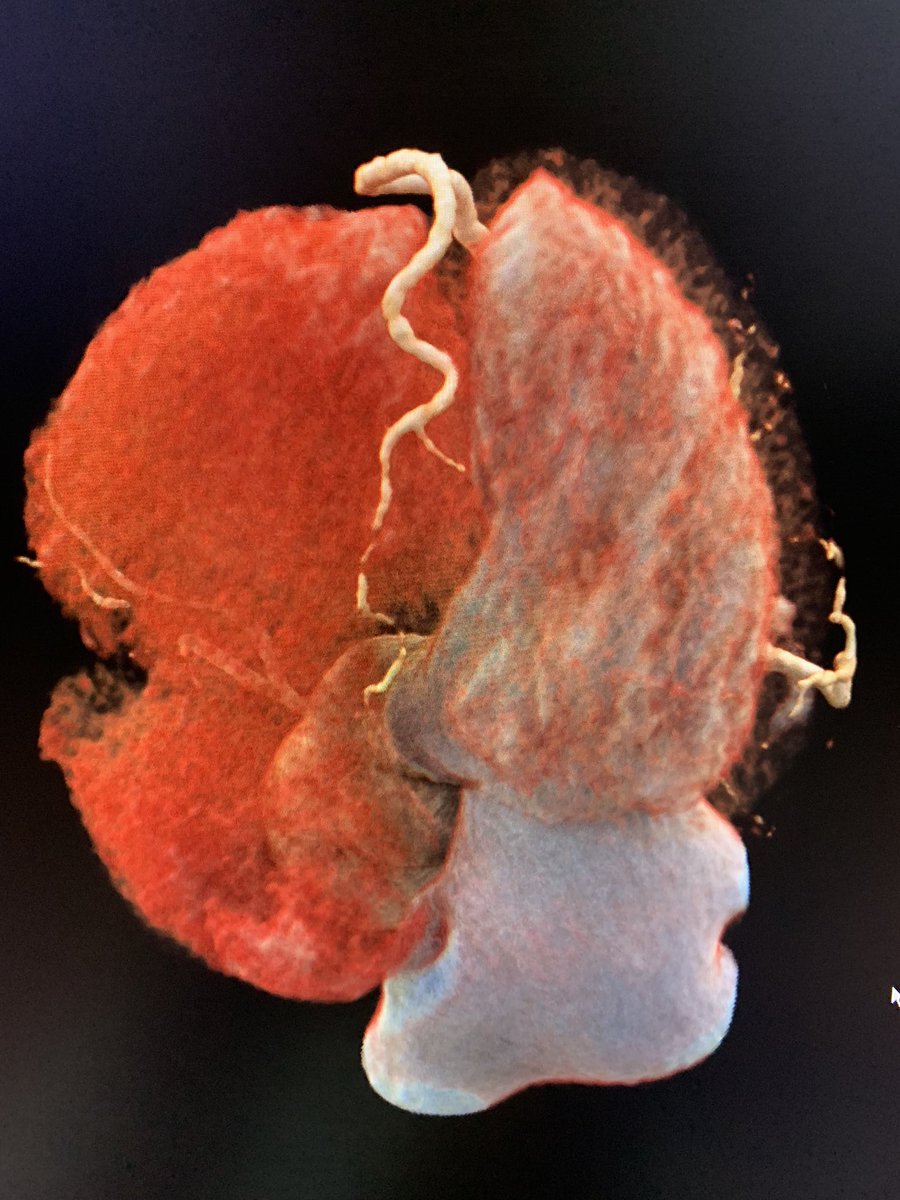

34 yo 👨🏻🦱 hypertrophic cardiomyopathy with anomalous papillary muscle. #whyCMR #cardioTwitter @benayozbay